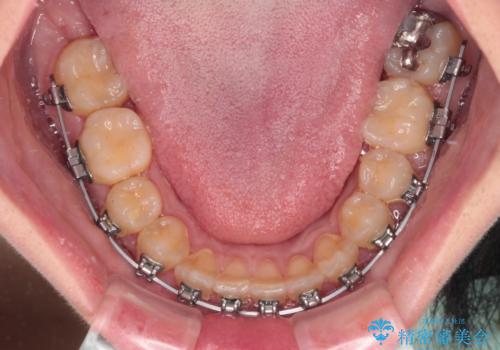

- 矯正装置

- メタルブラケット

このような咬み合わせの方の多くは、舌の突出癖が強い傾向にあり、反対咬合改善後に開咬となってしまい、なかなか治療が終わらないことがあります。

こちらの患者様は、舌のトレーニングを治療開始前から徹底的に実践していただき、僅か8ヶ月という短期間で治療を終えることができました。